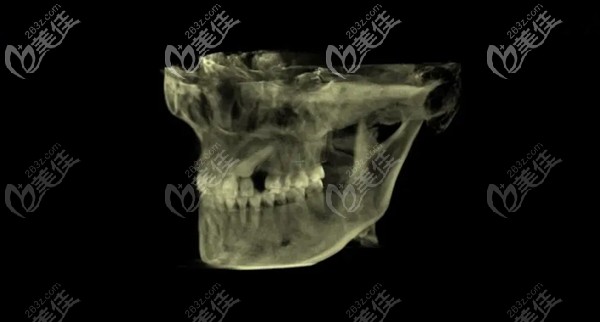

所以袁珂醫(yī)生讓她先拍個(gè)片子,看下具體口腔里的牙齒是啥樣的,沒想到具體的結(jié)果是醬紫的。

果不其然確實(shí)是少了一顆牙,但是我們也可以很清晰的看到漏洞地方里面還有一顆牙,只是這個(gè)牙是歪的。

經(jīng)過醫(yī)生分析講解后才明白,原來是因?yàn)樾r(shí)候的乳牙沒有掉,所以后來的尖牙沒有“萌出”而導(dǎo)致的。